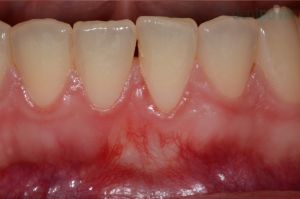

Ínyvisszahúzódás kezelése

Parodontológiai kezeléseink közé tartozik a visszahúzódott fogíny, más néven ínyrecesszió ellátása is. A fogíny a beavatkozást követően tökéletesen egészséges és ismét képes rá, hogy megvédje a fogat az esetleges károsodásoktól vagy a hideg-meleg ételek, italok okozta ingerektől!

1) Kiindulási helyzet

2) Ínyrecesszió fedése

Többszörös ínyvisszahúzódás kezelése

Páciensünk felső szemfogáról erősen visszahúzódott a fogíny, melynek következtében a fognyak szabaddá vált, ami fogérzékenységhez, fognyaki kopáshoz-, és szuvasodáshoz vezethet. Dr. Molnár Bálint parodontológus szakorvos ínyplasztika segítségével állította helyre a visszahúzódott fogínyt.

2) Többszörös ínyvisszahúzódás kezelése után